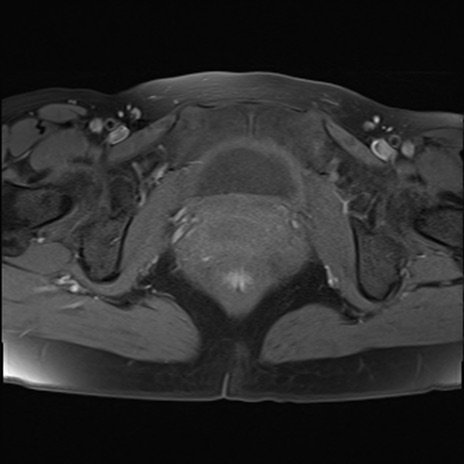

MRI(4日後)

T2WI(横断像)